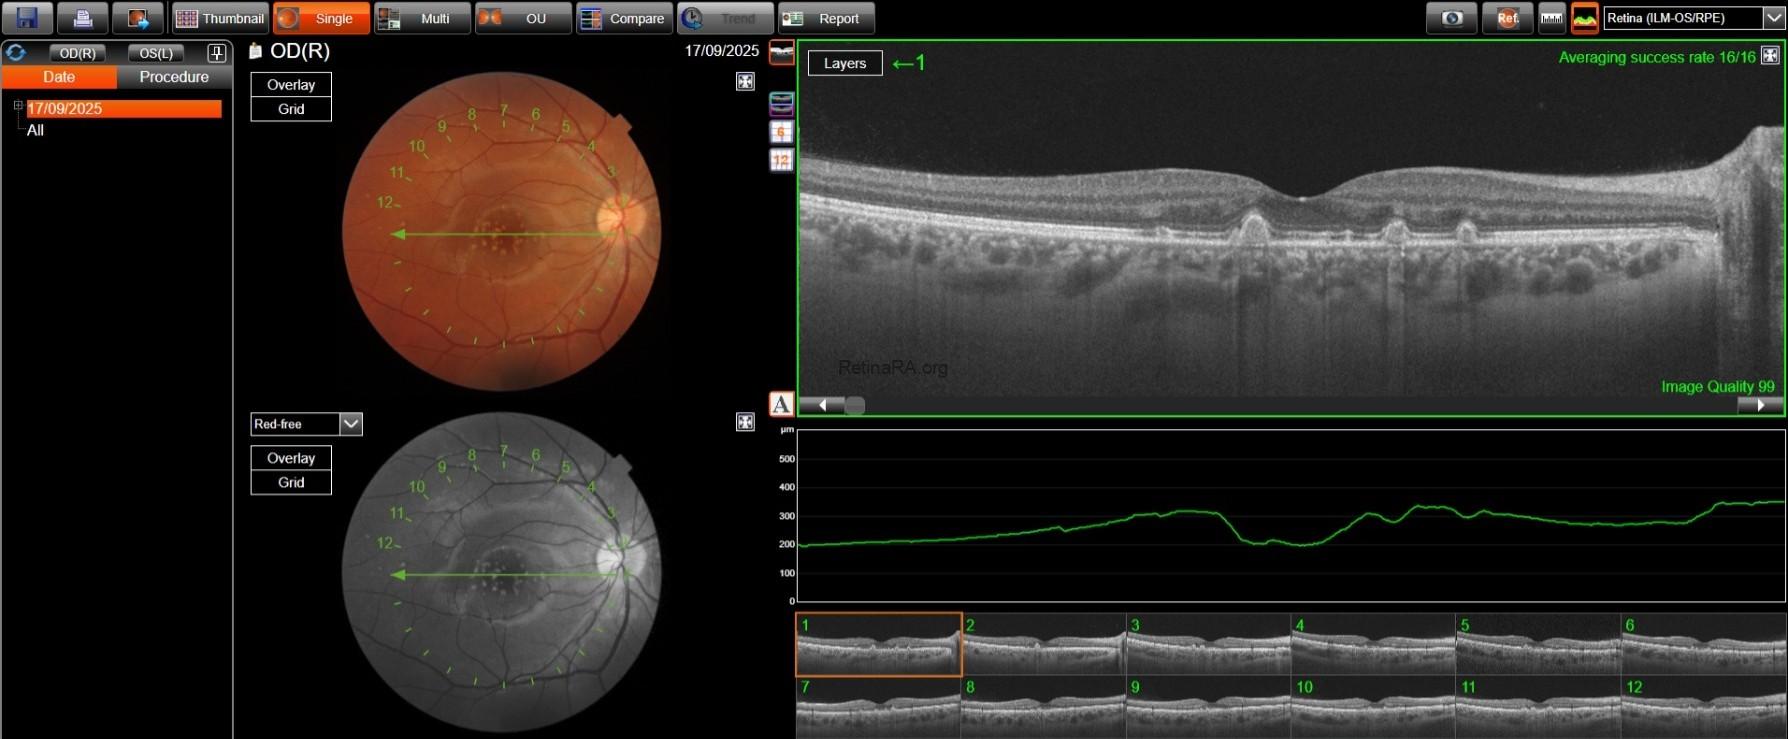

Fundus true-color photo shows multiple large yellowish drusen-like lesions scattered throughout the posterior pole and mainly clustered in the macular region in OU. On FAF, these lesions appear hyperautofluorescent with a surrounding hypoautofluorescent halo.

SD-OCT reveals dome-shaped RPE elevations with internal homogeneous medium reflectivity and increased central backscattering compared to their periphery; their size is variable, with the largest ones even deforming the overlying EZ band and possibly thinning the overlying retinal layers. No RPE and/or outer layer atrophy was found, as well as no subretinal and/or intraretinal fluid. OCT-A was unremarkable OU. En-face OCT segmented shows an hyperreflective center surrounded by a marked hyporeflective ring.

The patient already had an OCT performed in 2023, which showed complete stability of the lesions in both number and size.